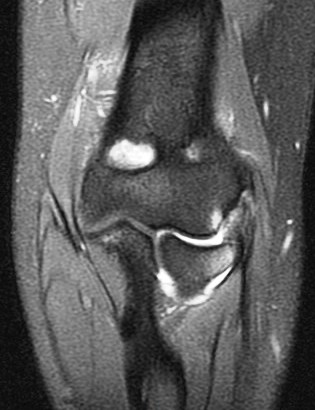

21 y/o F s/p wrestling injury. R/O acute radial head fracture.

Complex combination of valgus and varus stresses, probably a subluxation. Note the tear of the posterior lateral capsule just behind the ligamentous origin on the pdfs coronal. Patient should have posterolateral rotatory instability (PLRI). Also had extensor tendon strain with partial tear, trabecular injury of the coronoid process and of the humeral trochlea. Reference article.

Tear of combined origin of the lateral ulnar collateral ligament and radial collateral of elbow (RID2043)(RID2035)